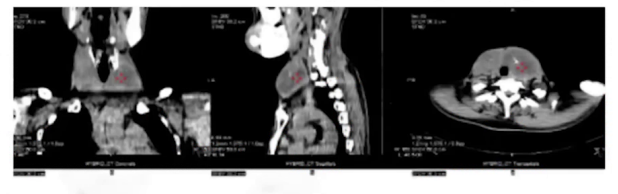

(3)影像学检查

ECT显像见甲状腺弥漫性病变,摄碘率增高。CT平扫显示甲状腺增大、密度不均、有钙化及颅面骨和上段颈椎骨纤维结构不良。

CT平扫显示甲状腺增大、密度不均、有钙化及颅面骨和上段颈椎骨纤维结构不良。